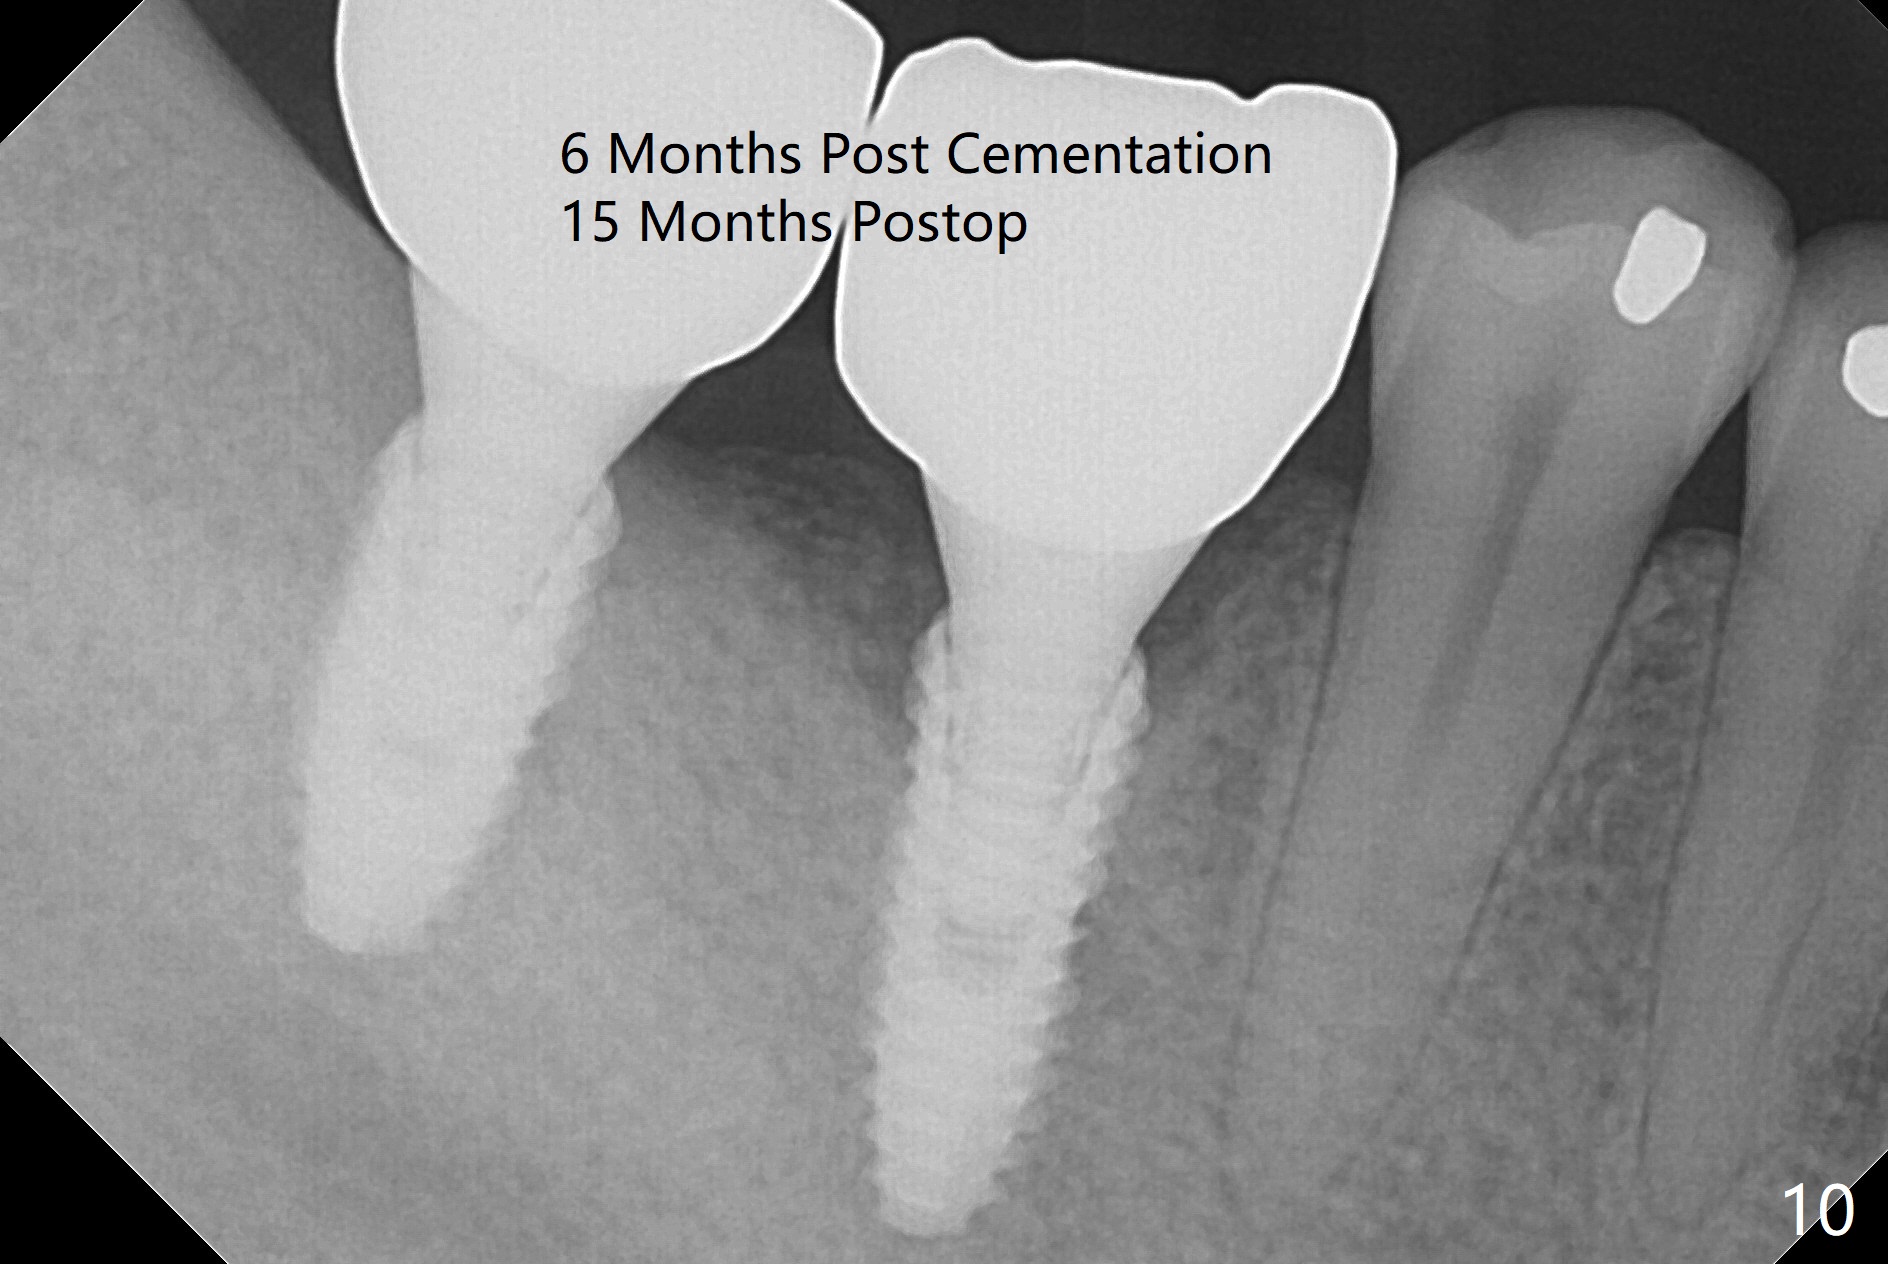

Infection is not so typical.  There is no recent postop X-ray, just 18-19 days postop.   Thanks for the reply.  We will keep watching.  The healing abutments, loose and associated with gingival inflammation, are removed 2.5 months postop (Fig.4).  There is crestal bone resorption, although the implants are stable.  The crestal bone resorption persists especially #30 distal 4 months postop (Fig.5 *).  When the implants are uncovered, there is mild bone loss distobuccal to #30 implant, consistent with early periimplantitis.  Bone graft is placed after debridement and healing abutment placement.  There appears no bone loss nearly 9 months postop (Fig.6).  The soft tissue looks healthy.  Cementation abutments (5.7x4(3) and 5.7x4.5(3) mm at #30,31, respectively) are placed for impression.  The distobuccal gingiva at #30 is hyerplastic 10 months postop (Fig.7 *, immediately before cementation), which is consistent with bone loss (Fig.8,9 * (periimplantitis)).  It is hoped that the infection will dissolve with improved oral hygiene (water pik) over the smooth final restoration.  In fact it is, i.e., the implants at #30 and 31 remain asymptomatic with the healthy gingiva 6 months post cementation (Fig.10,11).  There is mild crestal bone loss at #30 and 31 ten months post cementation (Fig.12).  Crown/implant ratio is the basis for screw loosening.  In fact the crown/abutment at #30 is loose 4 months later.  Incomplete seating of the abutment may be a culprit (Fig.12).  The gingival cuff is not healthy; a 6.8x7 mm healing abutment is placed with gingival blanching with Cetacaine and antibiotic ointment.  Next visit place a new smaller diameter abutment (4.5 or 5.2) with probably longer cuff (4 mm) or the existing abutment with no proximal contact crown, torque 25-30 Ncm and take BW with sensor 2 or PA with sensor 1.  In fact there is resistance to hand tighten a 4.5x4(4) mm healing abutment, which is due to contact with the mesial crest (Fig.13 *).  After use of 5.5 and 6.0 mm profile drills, the 6.8x7 mm healing abutment is reseated.  The latter appears to contact the mesial crest (Fig.14).  Later a 6x5 mm healing abutment is placed.  New crowns with new abutments are delivered 2 years 3 months postop (post Coronavirus lockdown).